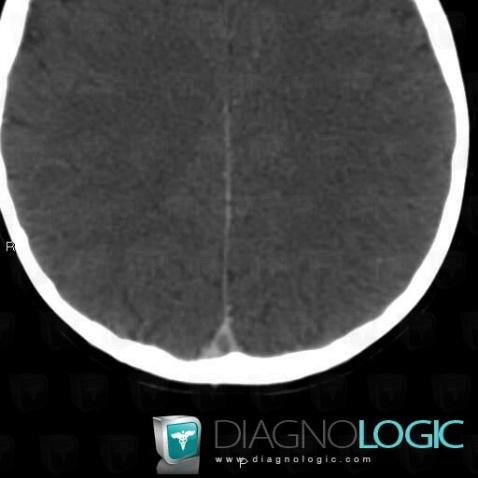

Thrombophlébite cérébrale, Veines cérébrales, Scanner

Voici les informations spécifiques à l'image clé ci dessus:

- Diagnostic Thrombophlébite cérébrale, Localisation(s) Veines cérébrales, comportant les gammes